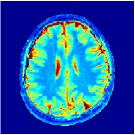

VI-E In-vivo experiments

Two sets of experiments were conducted here: first, we used the 2D and 3D acquisition sequences for scanning a healthy volunteer’s brain (real-world acquisitions). Figures 6 and 7 display the parametric maps reconstructed from 2D spiral and radial readouts. We computed the T1, T2 and proton density (PD) maps using baseline reconstruction algorithms ZF, VS, LR, FLOR, AIR-MRF and our proposed LRTV. While baselines use DM either for quantitative inference or also during reconstruction (i.e. AIR-MRF), we further compare the DM-free LRTV’s performance when cascaded to DM, KM and MRFResnet for quantitative inference. For the 3D spiral acquisitions we compared LRTV and its closest competitor VS in Figure 8. Outcomes from other tested algorithm are displayed in the supplementary materials (Figure S5). Since FLOR does not use dimensionality-reduction, our system ran out of memory during 3D reconstruction; hence results are not reported in this case.

VI-E1 Discussion

The LRTV-DM and LRTV-MRFResnet perform on par, and both outperform all tested baselines for reconstructing T1, T2 and PD maps in all acquisition schemes. This can be observed both visually in Figures 6, 7, 8, S2 and S3, and quantitatively in Table IV across all tested metrics. Other baselines were unable to successfully remove the under-sampling artefacts in TSMIs, and these errors propagated to the parameter inference phase and resulted in inaccurate maps. Temporal-only priors incorporated within LR are shown insufficient to regularise the inverse problem and LR sometimes (e.g. 2D spiral acquisitions) can admit solutions with even stronger artefacts than the model-free ZF baseline. This issue was previously studied for other non-Cartesian MRF readouts that similar to our spiral/radial trajectories, miss to sample the corners of the k-space in all timeframes (see section 2.2.2 and figure 2 in [19]). In the absence of reference for the k-space corners information, the LR iterations despite minimising the objective can converge to solutions with high-frequency artefacts, as visible in the computed maps. This highlights the need for adding an appropriate spatial-domain regularisation. FLOR reduces the LR’s artefacts but this improvement is limited because the suggested nuclear norm penalty does not incorporate an explicit spatial regularisation. Further for reducing artefacts, FLOR can introduce an undesirable bias in the computed T1/T2 maps e.g. see error maps in Figures S2 and S3. The non model-based VS baseline incorporates spatial regularisation and results in spatially smoother maps than ZF and LR, but it is unable to output artefact-free images. Further and consistent with our in-vitro experiment, we observe that VS overestimates the T2 values (e.g. in White and Grey matter regions) in tested 2D acquisitions i.e. the spatial regularisation trades off agains the quantification accuracy. The model-based AIR-MRF adds spatial regularisation through 2D/3D low-pass Gaussian filters however this trades off the sharpness of the computed maps and can increase the errors at the tissue boundaries (we searched Gaussian spreads that keep the blurs and high-frequency artefacts minimal). For our acquisition readouts, Gaussian filters performed better than disk filters of [19] for avoiding strong Gibbs artefacts. On the other hand, the spatiotemporally regularised LRTV greatly improves the TSMI reconstructions i.e. 4 dB enhancement compared to the closest competitor baseline (Table IV). This enables computing accurate and aliased-free multi-parametric inference using DM or the DM-free learning-based alternative MRFResnet as visible in Figures 6, 7, 8, S2 and S3. MRResnet and DM score competitive quantitative inference results i.e. T1 and T2 MAPE less than 5% and 9%, respectively (Table IV). KM also outputs comparably accurate T1 maps, however this shallow learning model despite having a model size larger than MRFResnet, is unable to learn accurate T2/PD quantification and it results in poor estimated maps, consistent with our observations in section VI-C.